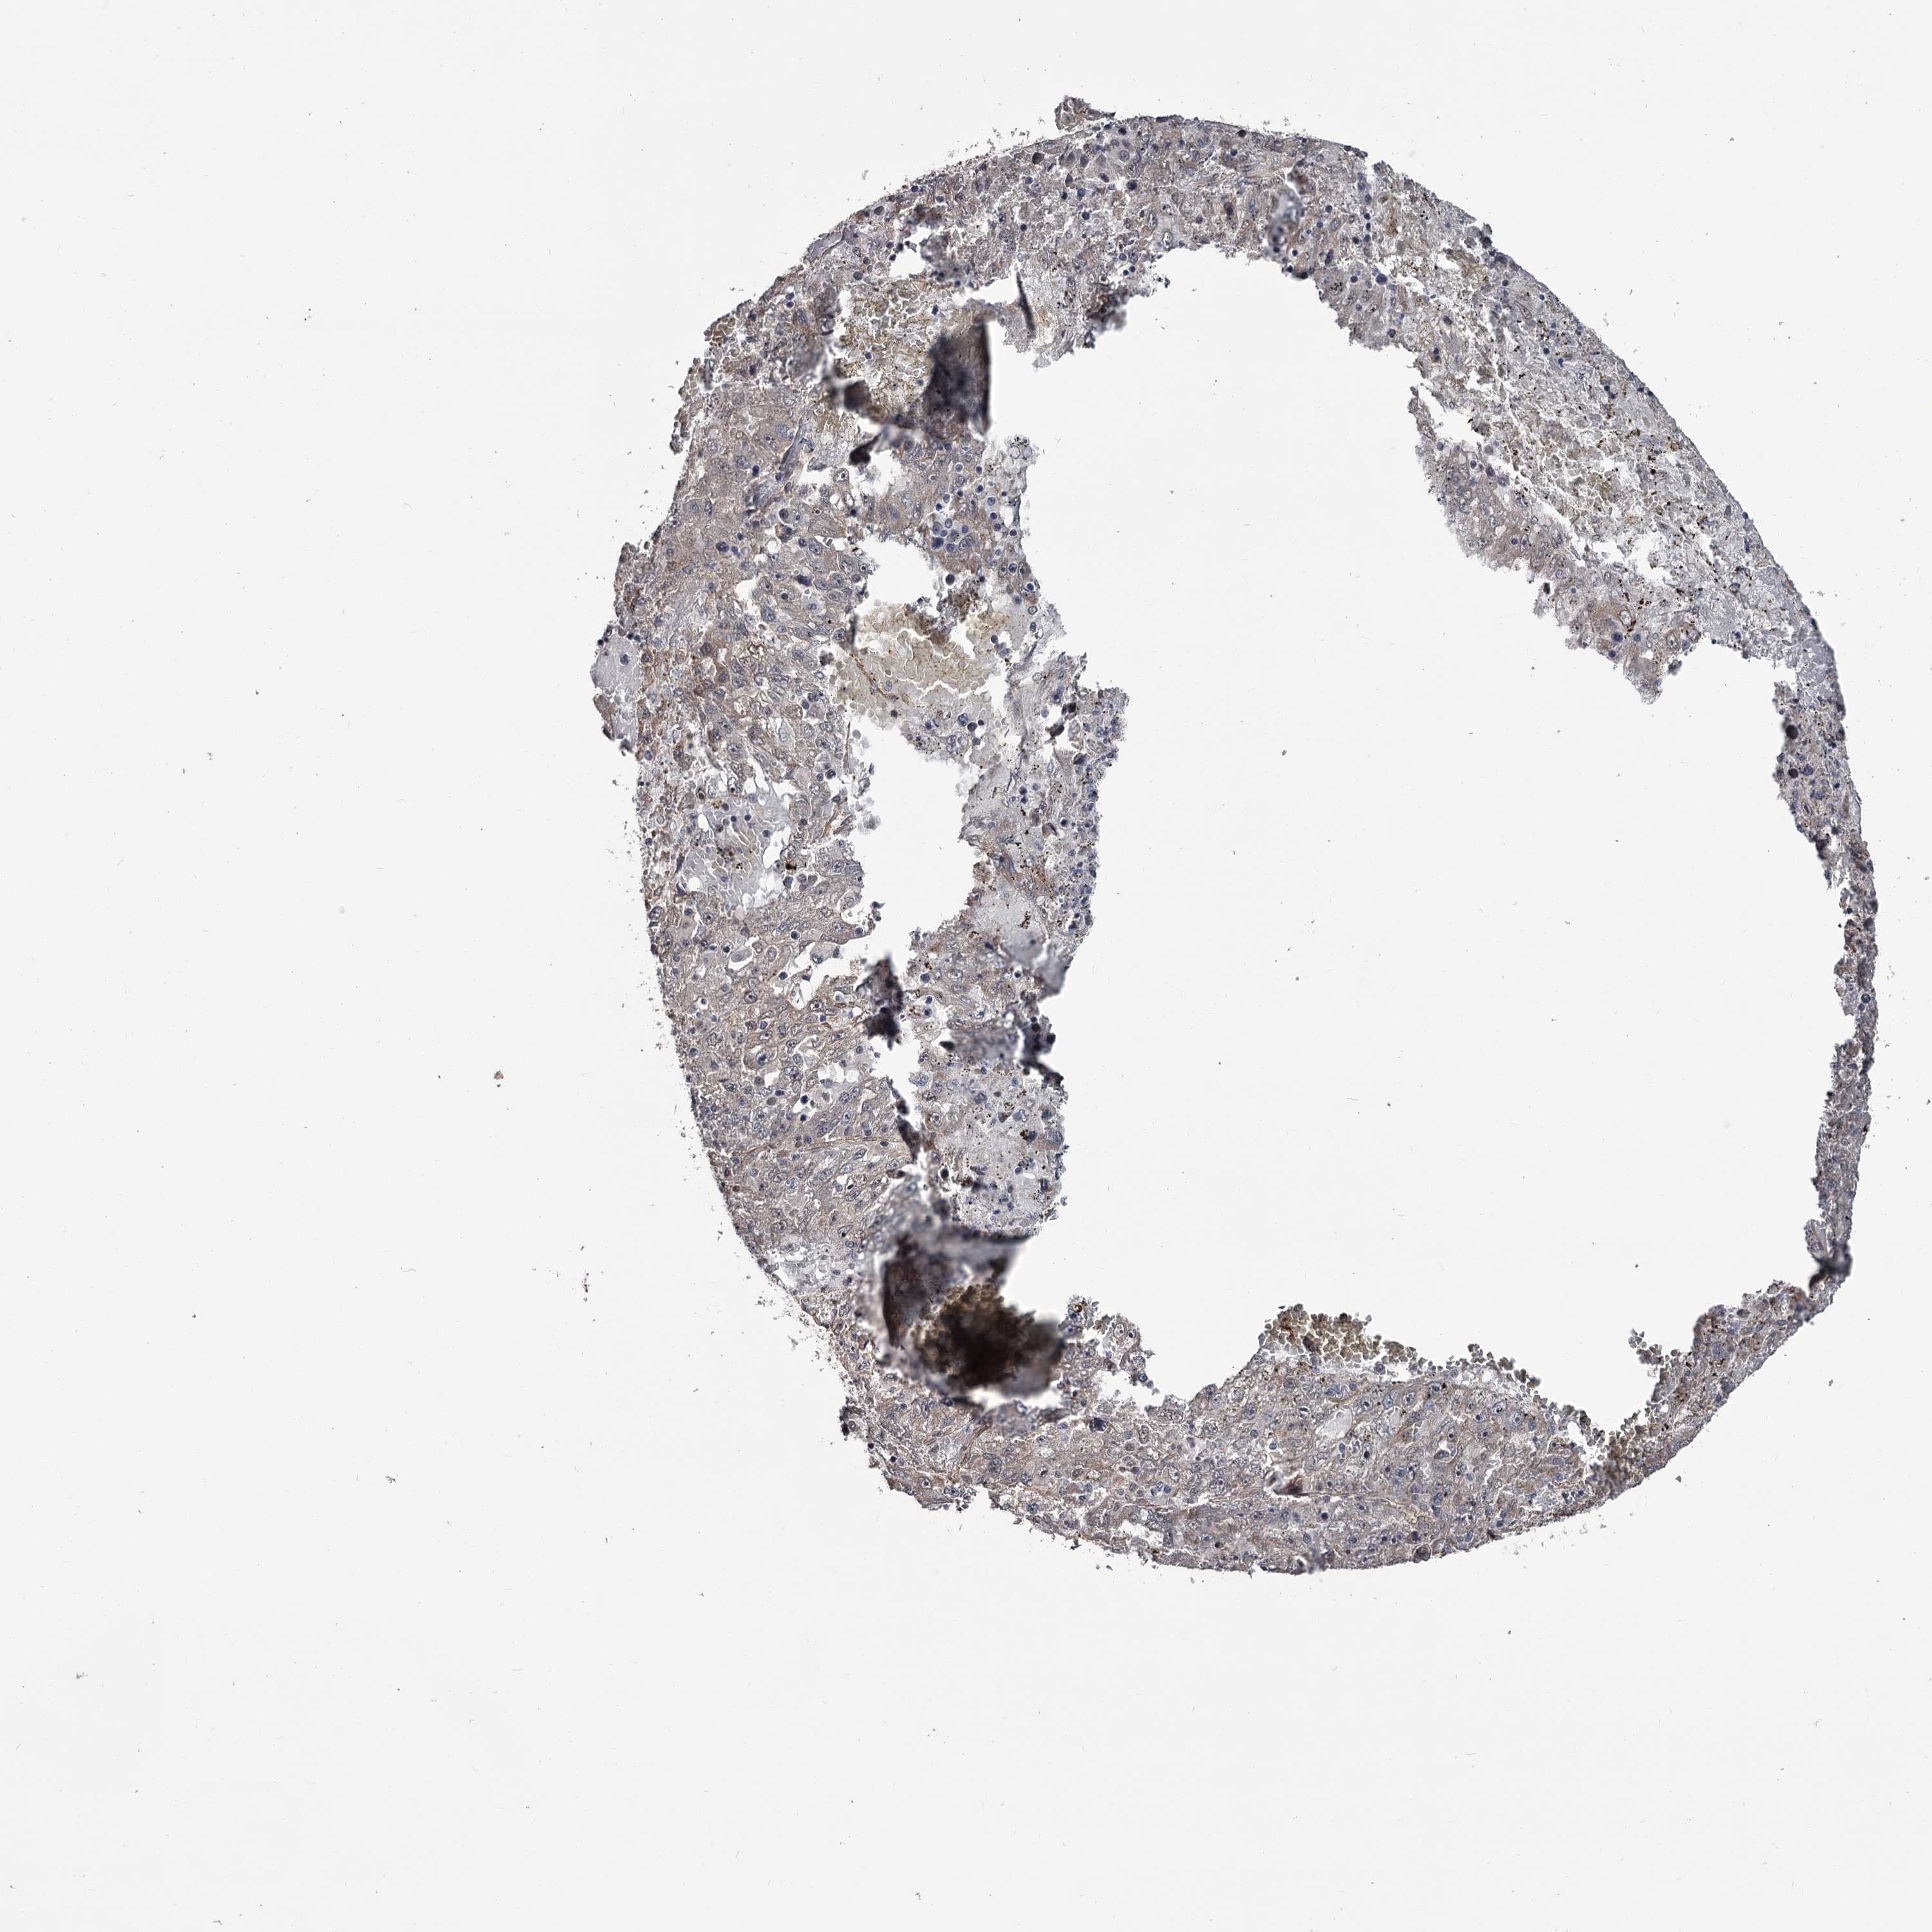

LIVER CANCER - Protein expressioni

A mouse-over function shows sample information and annotation data. Click on an image to view it in a full screen mode. Samples can be filtered based on level of antibody staining by selecting one or several of the following categories: high, medium, low and not detected. The assay and annotation is described here.

Antibody stainingi

Antibody staining in the annotated cell types in the current human tissue is reported as not detected, low, medium, or high, based on conventional immunohistochemistry profiling in selected tissues. This score is based on the combination of the staining intensity and fraction of stained cells.

Each image is clickable and will lead to virtual microscopy that enables deeper exploration of all samples and also displays staining intensity scores, fraction scores and subcellular localization as well as patient and tissue information for each sample.

Antibody HPA038562

Staining

High

Medium

Low

Not detected

Intensity

Strong

Moderate

Weak

Negative

Quantity

>75%

75%-25%

<25%

None

Location

Nuclear

Cytoplasmic/membranous

Cytoplasmic/membranous,nuclear

Cholangiocarcinoma

Carcinoma, Hepatocellular, NOS